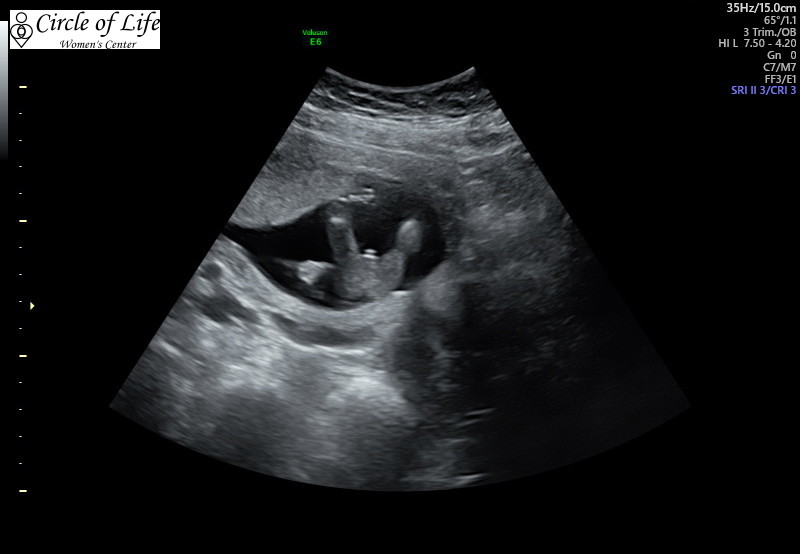

For sure a boy??

I had this scan done at 13w3d (baby measured a day behind) and doctor said for sure 100% boy. It looks like a boy to me but have never had someone try to guess so early. I showed it to a friend who said that the slightest wrong angle can make swollen labia look like a boy and to not get too attached to the idea. Does this look like its going to stay a boy or could this be swelling??

Do you have any side on pics of the baby? Potty shots aren’t very reliable at that gestation. Swollen girly parts can be mistaken for a penis lol

Potty shots are not reliable at that stage of gestation. To me that looks like it could easily be a clitoris. Did the doc look at other angles or just at the potty shot?? Doctors are the absolute WORST guesses and give by far and away the most incorrect ultrasound gender guesses.